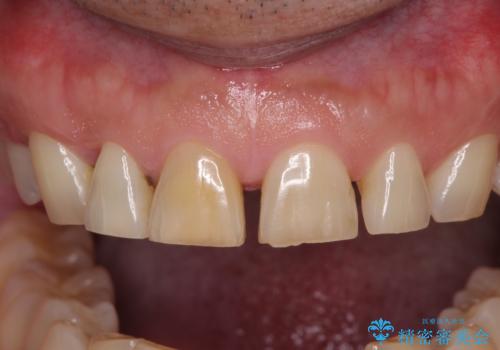

- 前歯の目立つ隙間を気にして来院された患者様です。

高校生の頃に矯正治療を行ったものの、強い咬合力により上顎が拡大され、正中に隙間ができてしまいました。

通常では歯の周囲全体を削った上でクラウンを装着することが多いのですが、咬合力が非常に強く、クラウンではセラミックが欠けてしまう可能性が考えられたため、咬合を変えることとのないラミネートベニアにて治療を行うこととしました。

ラミネートベニアは切削量が少ないことがメリットとしてあげられますが、色調を周辺と合わせられないこと、接着境界線が長く汚れや歯石が溜まりやすいことがデメリットとして考えられます。

また、接着境界線にむし歯がある場合には適用外となるなど、適用症例を選ぶため、治療に際して担当医としっかりと相談することが大切です。